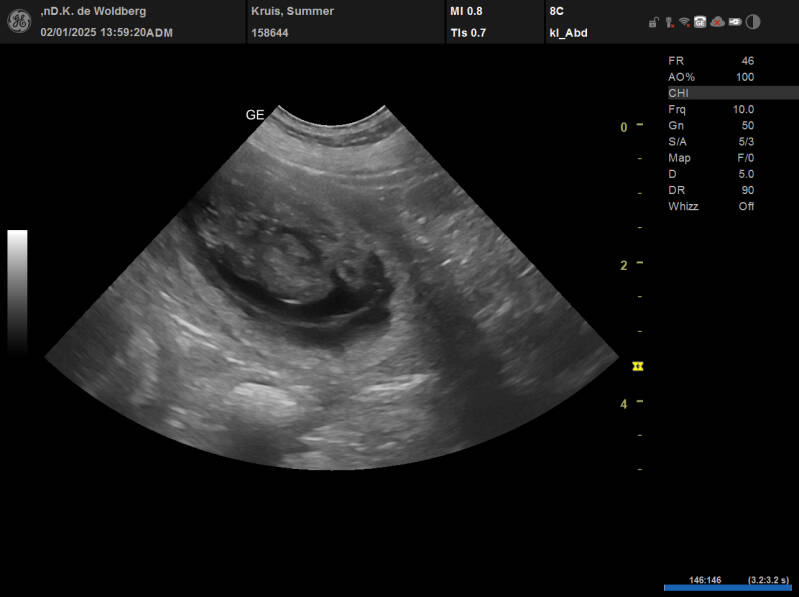

De Echoscopie van de Dracht

Het drachtige buikje